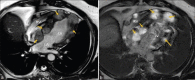

Cardiac Metastasis of Malignant Melanoma